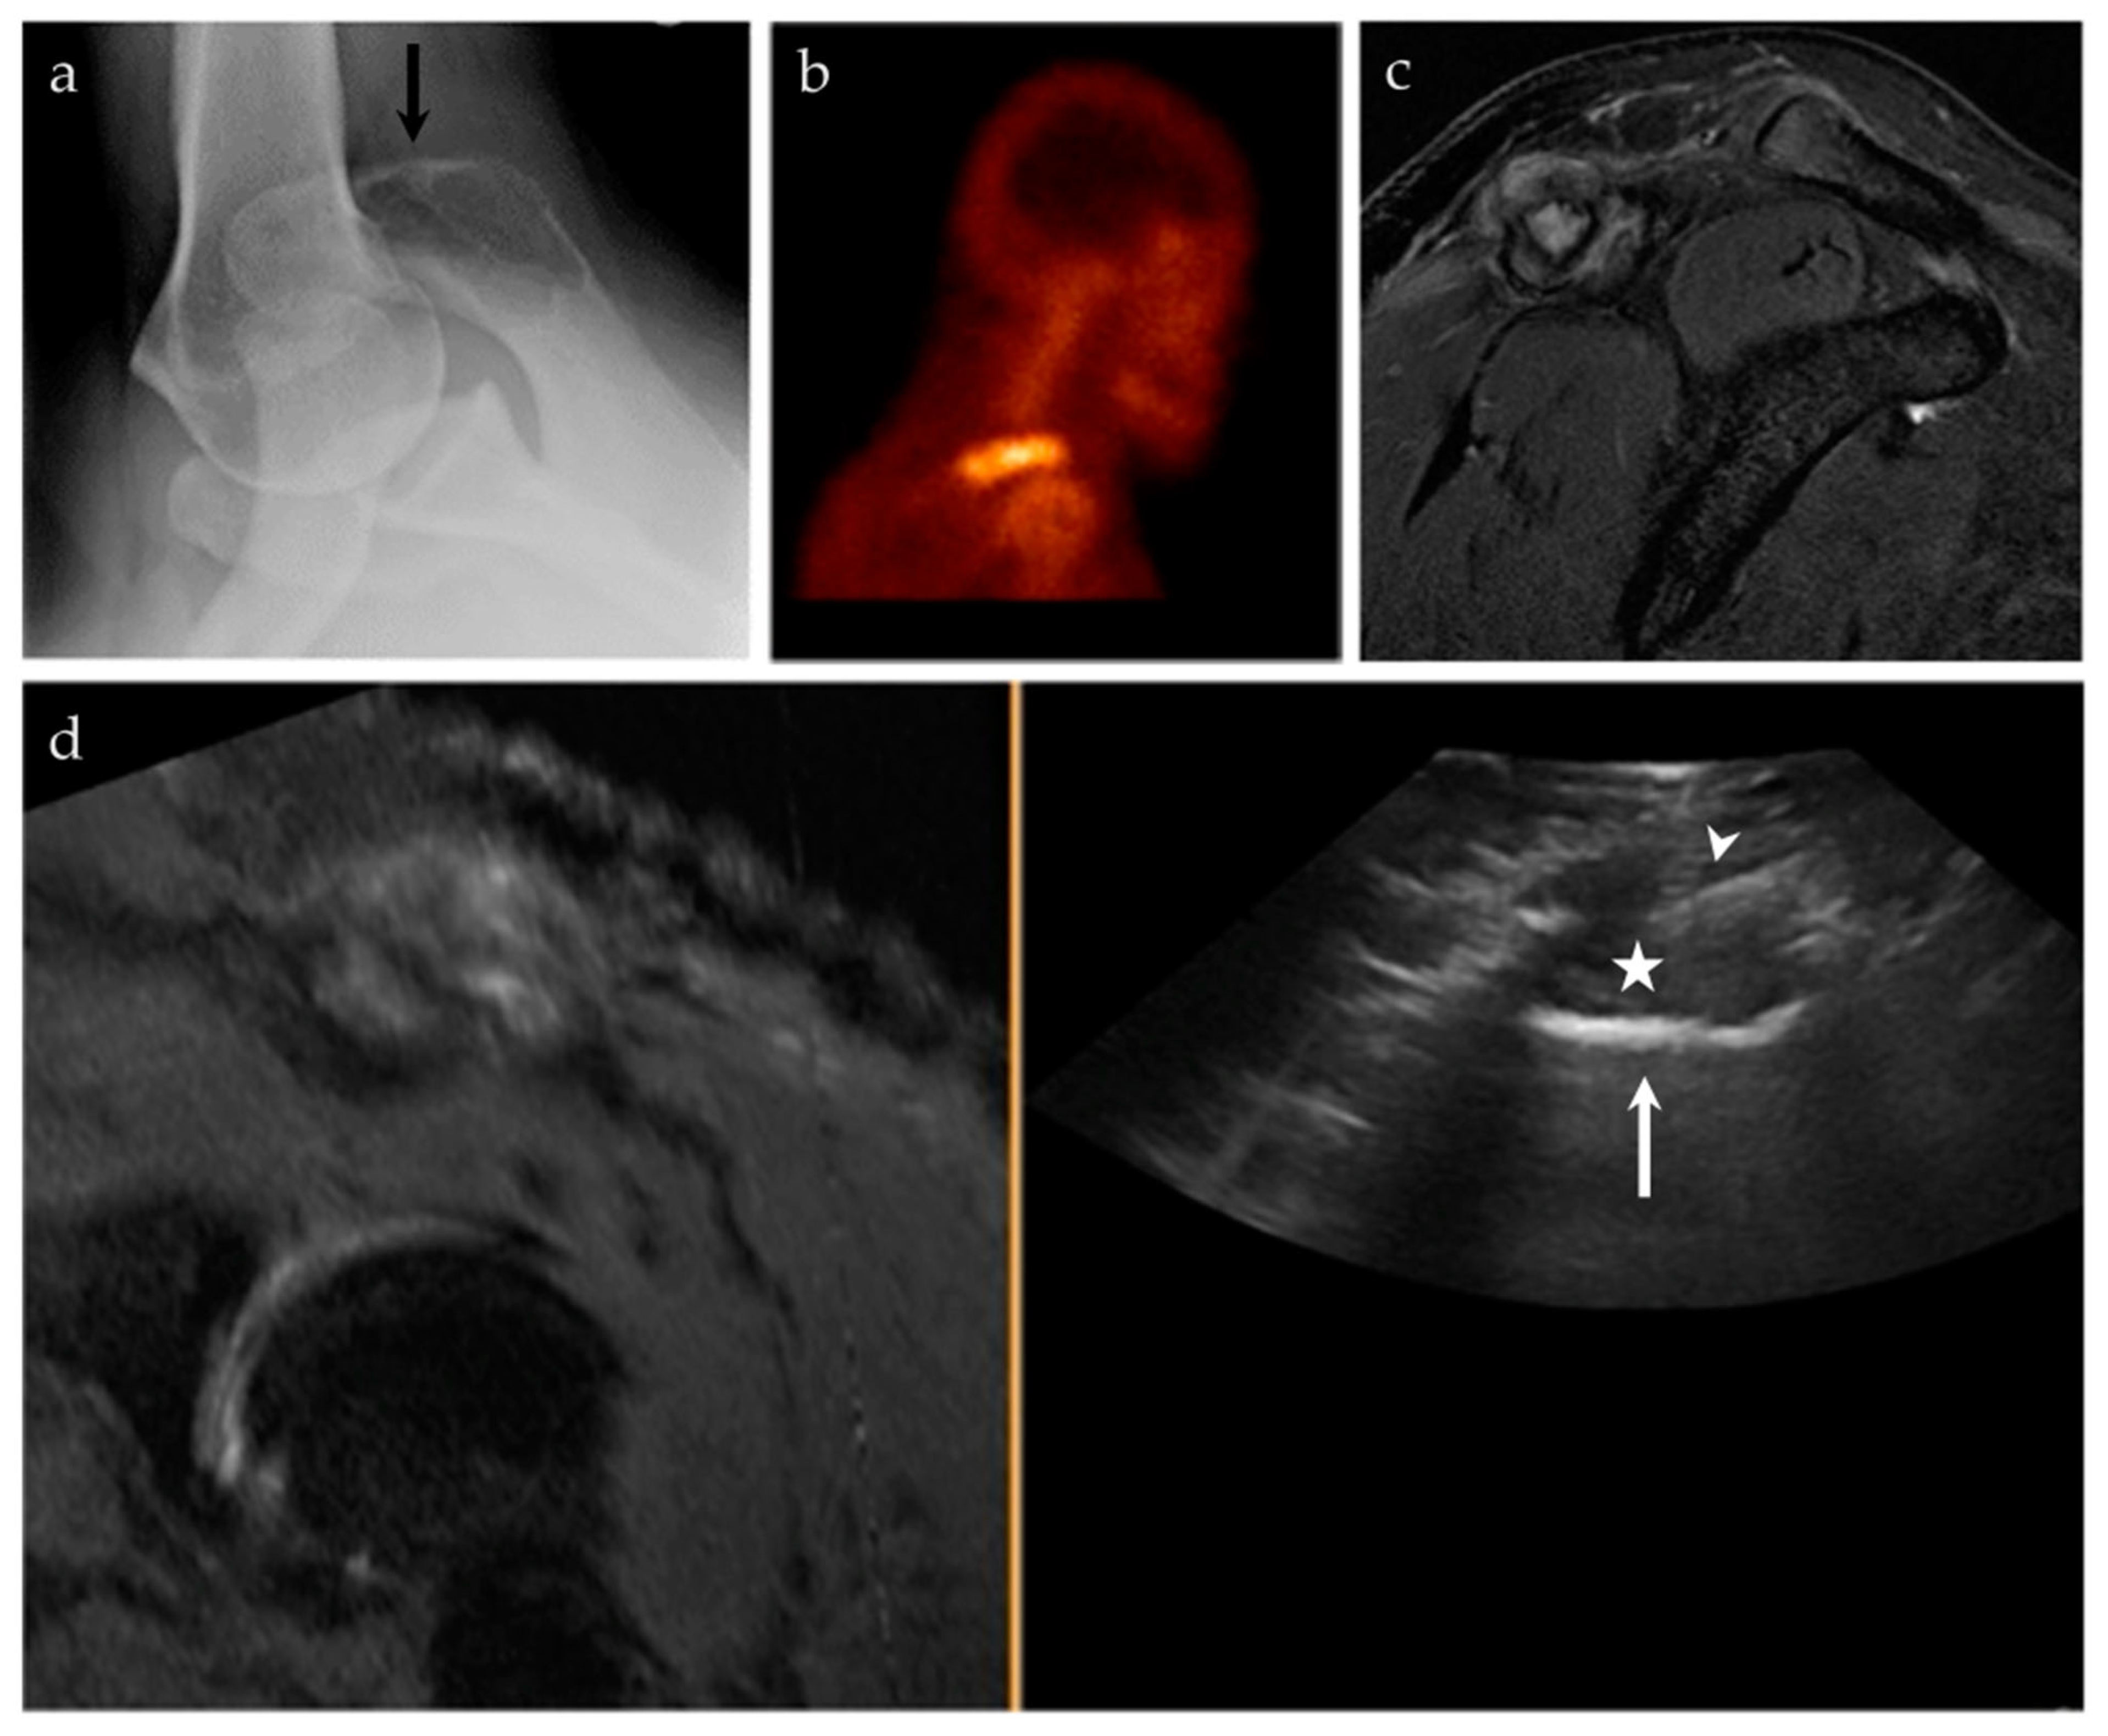

3.2.4. Targeted Percutaneous Lesion Biopsy and/or Aspiration

| 17/M | Acromioclavicular joint | US-MRI | Metastatic disease, nasopharyngeal carcinoma | Neoplastic, malignant |

| 45/M | Right acromion | US-MRI | Epithelioid hemangioma | Neoplastic, benign |